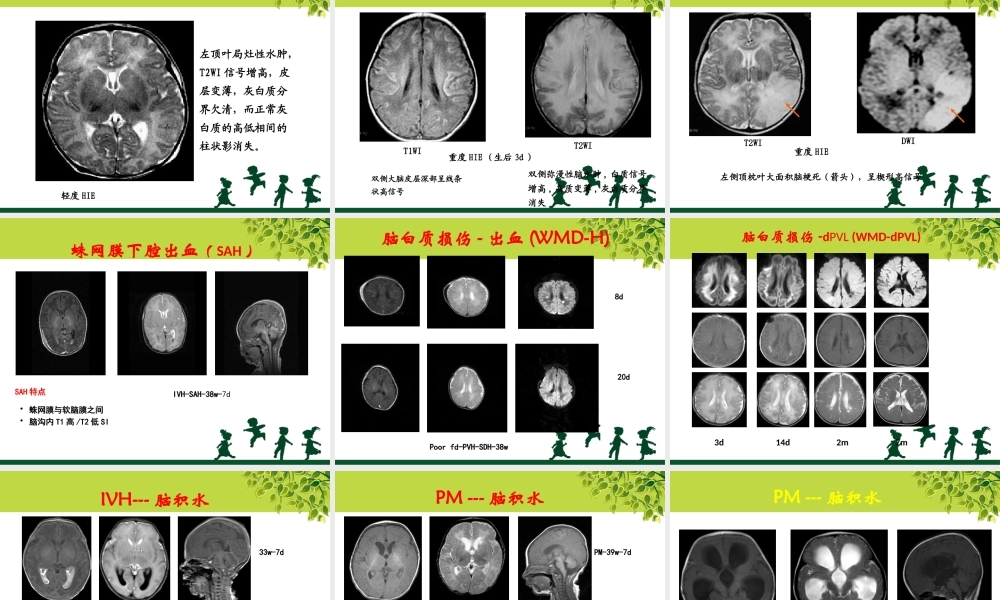

儿童康复的相关检查相关检查•1、CT•2、MRI•3、脑电图•4、听觉诱发电位•5、视觉诱发电位•6、肌电图•7、表面肌电图CT•影像学检查:直观显示脑结构的异常改变•部位:头颅、脊柱、颞部•检查需要睡眠CT优点•快速、安全、无创地显示脑的形态改变•对新生儿、早期脑损伤患儿有临床意义•对脑出血、钙化、骨化具有可靠的诊断意义CT缺点•具有辐射性,有一定的损害•分辨率较MRI差6轻度:散在或局限性低密度改变,在2个脑叶以内7中度:低密度改变超过2个脑叶,灰白质对比模糊中度不伴出血中度伴出血8•重度:弥漫性低密度改变,灰白质界限失,•脑室受压。中、重度HIE常伴ICH。颅内出血CT扫描弥漫性脑水肿室管膜下出血(箭头)左额叶局限性水肿(箭头)CT扫描脑室内积血(箭头)额叶白质水肿大脑弥漫性水肿蛛网膜下腔出血(箭头)MRI优点•良好的软组织对比、高分辨率、无创伤、无痛、无放射、可以多方位扫描,能够直观显示颅脑的形态学改变。•对白质的发育过程、脑白质病变有诊断意义•能对血管病变诊断MRI缺点•成像速度慢,运动伪影对,对婴幼儿睡眠要求高•钙化灶易漏诊头颅MRI脑室系统较小呈裂隙状,灰白质分界清楚,呈高低信号相间的柱状影,内囊后肢的后部及丘脑腹外侧均呈低信号正常足月新生儿基底节层面T2WI表现头颅MRI轻度HIE左顶叶局灶性水肿,T2WI信号增高,皮层变薄,灰白质分界欠清,而正常灰白质的高低相间的柱状影消失。头颅MRI重度HIE(生后3d)T1WIT2WI双侧大脑皮层深部呈线条状高信号双侧弥漫性脑水肿,白质信号增高,灰质变薄,灰白质分界消失头颅MRI重度HIET2WIDWI左侧顶枕叶大面积脑梗死(箭头),呈楔形高信号•蛛网膜与软脑膜之间•脑沟内T1高/T2低SISAH特点IVH-SAH-38w-7d蛛网膜下腔出血(SAH)Poorfd-PVH-SDH-38w20d8d脑白质损伤-出血(WMD-H)3d脑白质损伤-dPVL(WMD-dPVL)14d2m7m33w-22dIVH---脑积水33w-7dPM-39w-28dPM---脑积水PM-39w-7dPM-39w-6mPM---脑积水细菌性脑膜炎皮层受累---大肠埃希菌脑梗死---阴沟肠杆菌脑脓肿---白色念珠菌感染脑电图•电生理的一种•反映脑电波的情况•无创、安全•癫痫诊断的金标准脑电图国际标准10—20系统头皮电极放置位置。21个标准电极正常清醒及睡眠期脑电图EEG:48天婴儿清醒期。正常EEGEEG:48天婴儿清醒期。正常EEG听觉诱发电位•电生理•无损伤、客观性强、稳定性好•反映听神经功能的生理和病理现象•需深度睡眠定义•给予声音刺激,在头皮上所记录到由听觉神经通路所产生的电位ABR...